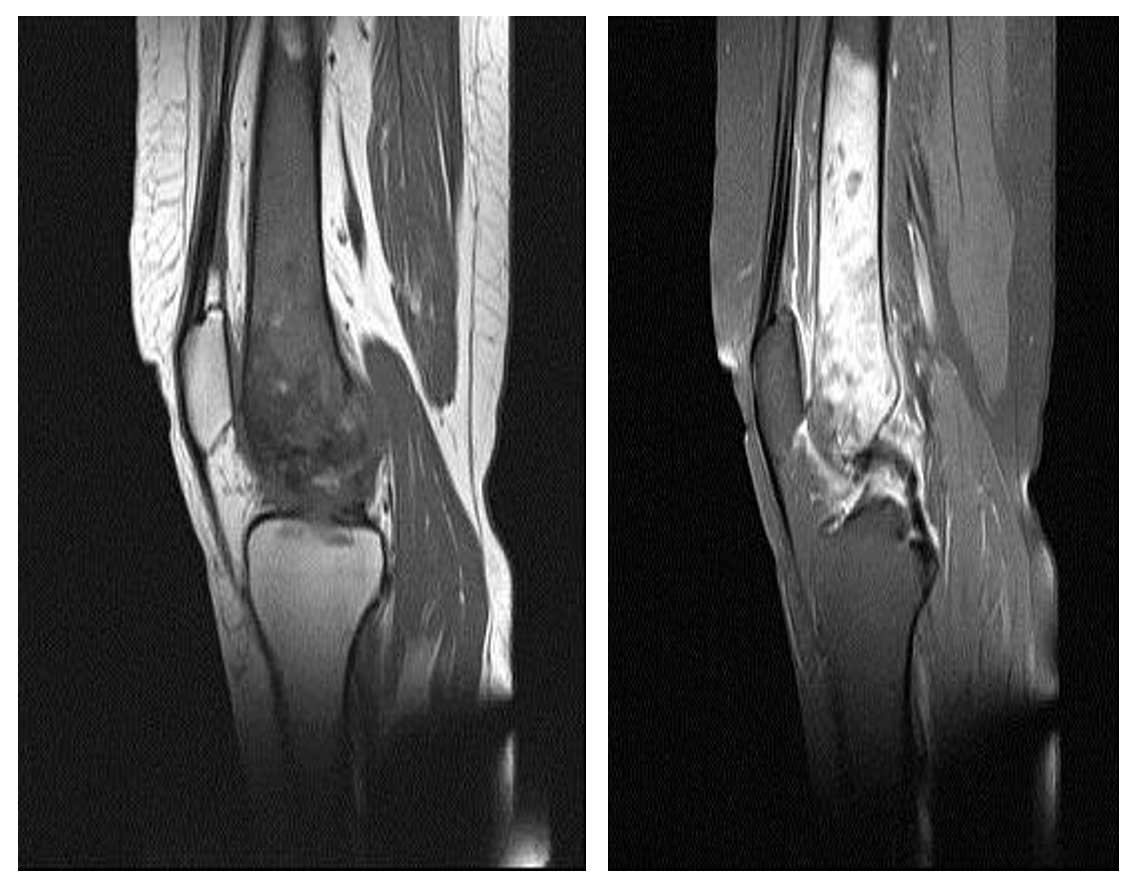

Ameliyat Öncesi: MR’da aynı lokalizasyonda kemiğin içini dolduran tümör dokusu ve çevreleyen ödem görülmekte.